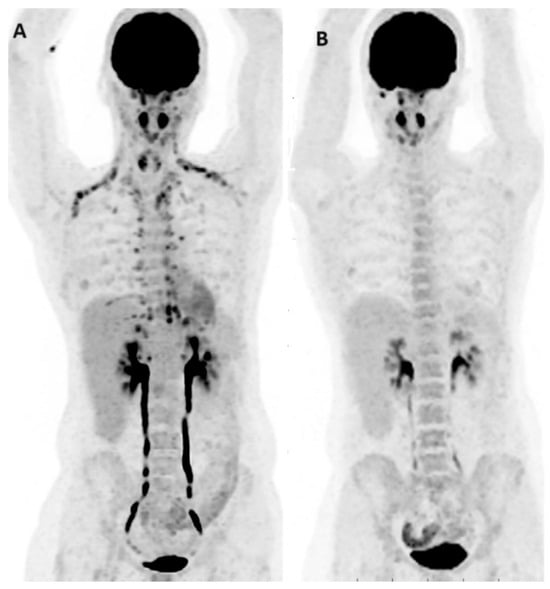

- Nguyen, A.; Fullard, K.; Sheehan-Dare, G.; Tang, R.; Chan, L.; Ho, B.; Emmett, L. Diagnostic value of 68Ga-DOTATATE PET-CT imaging for staging of ER+/PR+ HER2- breast cancer patients with metastatic disease: Comparison with conventional imaging with bone scan, diagnostic CT and 18 F-FDG PET-CT in a prospective pilot trial. J. Med. Imaging Radiat. Oncol. 2022, 66, 731–737. [Google Scholar] [CrossRef] [PubMed]